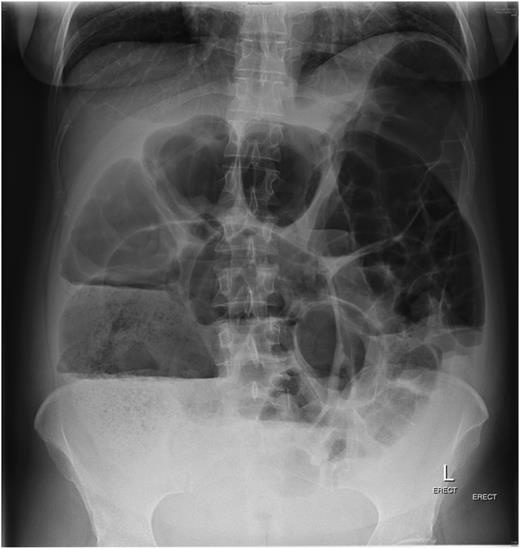

The patient failed to have a return of normal bowel function post-decompression and after 3 days was administered 500 µg of neostigmine via subcutaneous injection in an attempt to improve bowel motility. That evening she developed fever, and abdominal pain and erect chest X-ray confirmed free gas under her diaphragms (Fig. 3). She was taken to theatre for emergency laparotomy. At operation she was found to have two sites of caecal perforation with a moderate faecal contamination in the right paracolic gutter. A right hemicolectomy with primary anastomosis was performed. She was discharged home on post-operative Day 7 without further complication. It is possible that the serosal tears of the caecum had occurred secondary to either administration of neostigmine or dilatation in the post-Caesarean period.